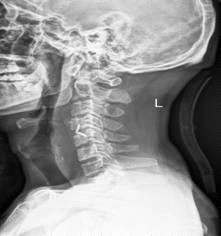

中年男性41歲,因“行走不便2年,加重伴雙手麻木2周”之主訴入院,癥狀主要為:頸部疼痛、僵硬,雙下肢無力、行走不穩(wěn),雙手麻木,協(xié)調性差,右手握筆困難。入院查體:步態(tài)不穩(wěn),C3-C7壓痛、叩擊痛,肢痛溫覺減退,雙上肢肢肌力5-級,雙下肢肌力4-級,肌張力增高,雙下肢腱反射亢進,病理征(+),行頸前路小切口突出椎間盤切除、前路頸椎橋形鎖定植骨融合(ROI-C假體),無需前路鋼板,術后四肢麻木明顯緩解,右上肢精細動作明確增強,可寫字,行走不穩(wěn)消失,肌力基本正常,頸部活動度無明顯受限。(圖1、圖2)

圖2:術后頸椎X線提示頸椎橋形鎖定融合居中,椎間隙高度恢復正常,融合良好。